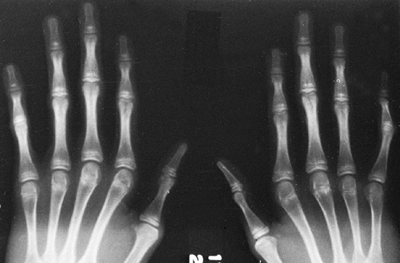

Arachnodactyly is defined, for purposes of radiographic readings, as an

increase in the ratio of length to width of the second to fifth

metacarpals (Fig. 9.2). The average ratio of

the lengths of the second to fifth metacarpals, divided by the widths

of the respective diaphyses, is greater than 8.8 in male patients and

greater than 9.4 in female patients with Marfan syndrome (21).

Figure 9.2 Hands showing arachnodactyly. Notice the long, thin metacarpals and phalanges.